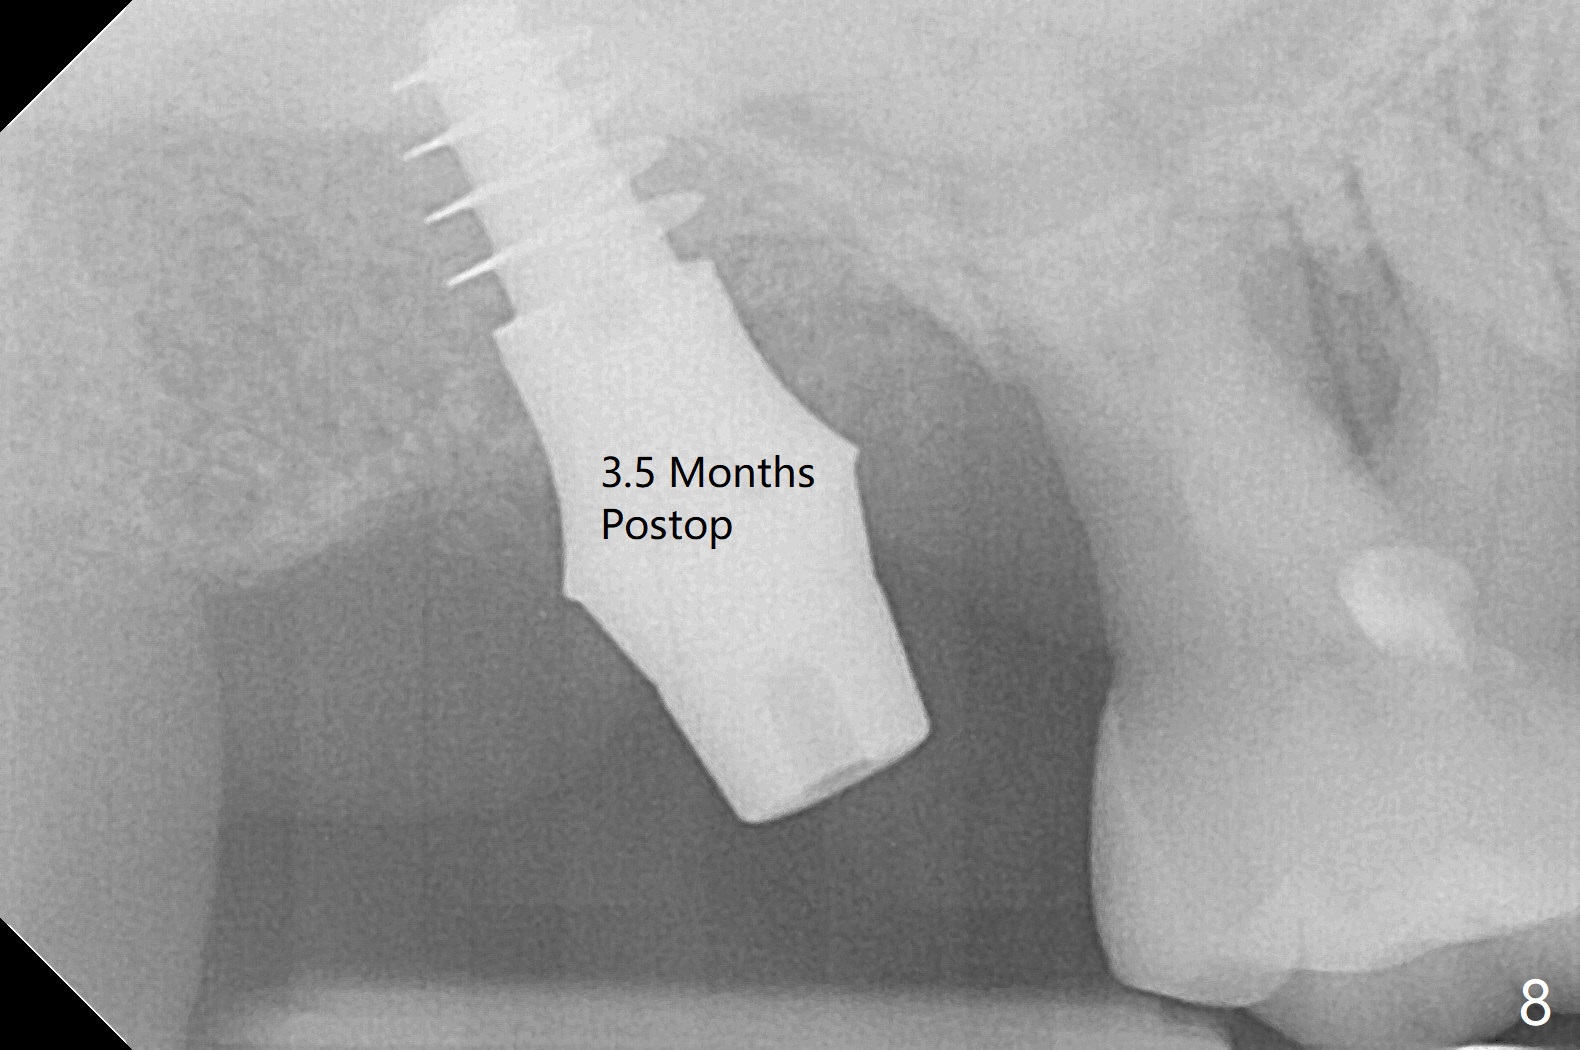

After extraction of the tooth #2 (Fig.1), osteotomy is supposed to be initiated in the mesial slope (Fig.2 arrow). With Magic Expanders (3-4.8 mm), osteotomy ends up in the bottom of the socket (Fig.3). Trajectory is found to be off when 4x9 and 5x9 mm dummy FC implants are placed with stability (Fig.4,5). The final implant, Magicore (5x7(3)mm, >29 Ncm), appears to be placed too deep for restoration (Fig.6,7); a screw retained crown may be a solution. PRF membrane and Vanilla (allograft) are used for sinus lift (no sinus membrane perforation). Following Vanilla graft in the socket gap (Fig.6 *), another piece of PRF membrane is used to cover socket opening. The membrane is fixed in place with suture and periodontal dressing. The implant seems to have osteointegrated 3.5 months postop (Fig.8). After change to 4.3x5 mm solid abutment and mesial surface adjustment, impression is taken for early loading because of removal of #14 implant. In fact the patient is satisfied with mastication improvement at #2 later on.